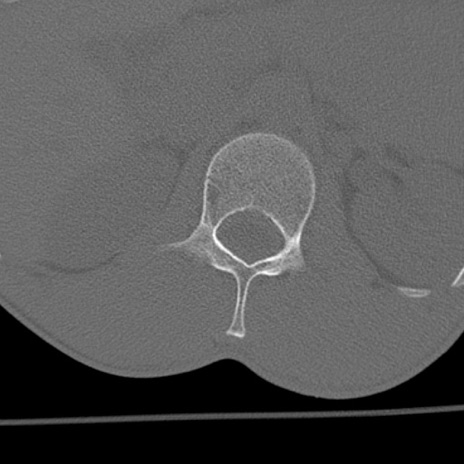

症例3 腰椎CT(横断像)

腰椎CT